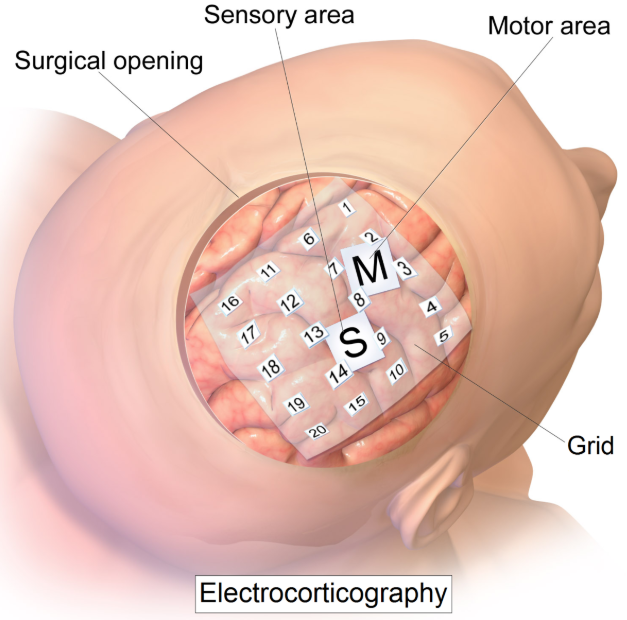

ECoG

皮质电描记术使用放置在大脑裸露表面上的电极来测量大脑皮层的电活动。1950年代,它在蒙特利尔神经病学研究所首次使用。这被称为半侵入式,但仍需要开颅手术植入电极。因此,仅在出于医学原因(例如癫痫病)需要进行手术时才使用它。

电极可置于硬脑膜外(硬膜外)或硬脑膜下(硬膜下)。条状或网格状电极覆盖了皮质的大面积区域(从4到256个电极)[2],从而可以进行各种各样的认知研究。

图片来自[3]